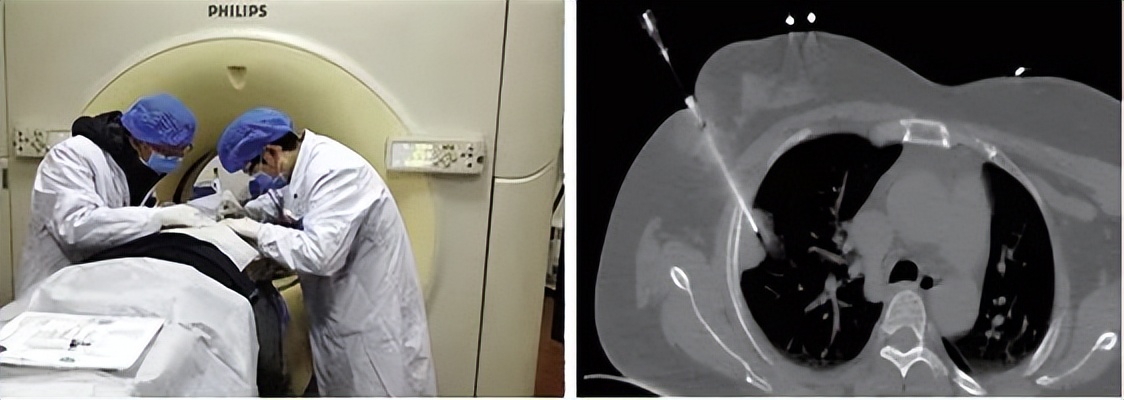

3、 经胸壁诊断技术

针对肺外周病变的诊断,我们熟练开展了CT及B超引导下经皮肺穿刺活检术,阳性率更高,创伤更小、费用更低廉。